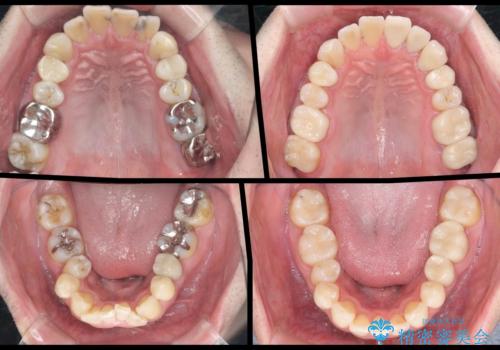

臼歯部メタルフリー再補綴

- 治療してからの年月が経過し、かみにくくなったブリッジ・クラウンを全てやりかえたいと希望され来院されました。

クラウン・ブリッジを作り替えるにあたり虫歯の徹底的な除去・根管治療のやり直しを行い今後やり直しをしなくて済むような環境を整えていきます。

- 110万円(仮歯×8・ファイバーコア×6・ジルコニアクラウン×8)費用は治療当時の料金となります

装着して長期間経過したブリッジやクラウンは隙間から細菌が侵入し虫歯が再発してしまっていることがあります。

長期的に問題のないブリッジ・クラウンを作製するため、虫歯をしっかりと除去すること精密な根管治療を行うことが肝要です。